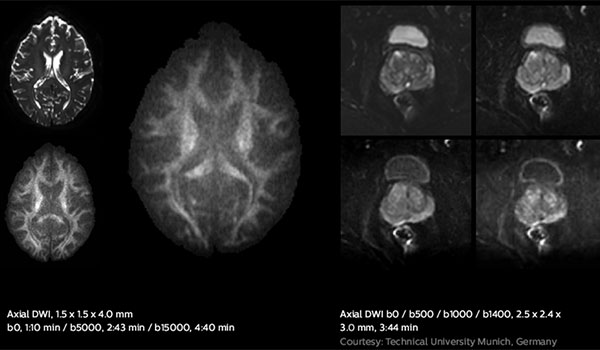

Fast diffusion scans

Elition 3.0T new high-performance gradients enable fast diffusion scans with high SNR, relevant for tissue characterization and treatment response monitoring.